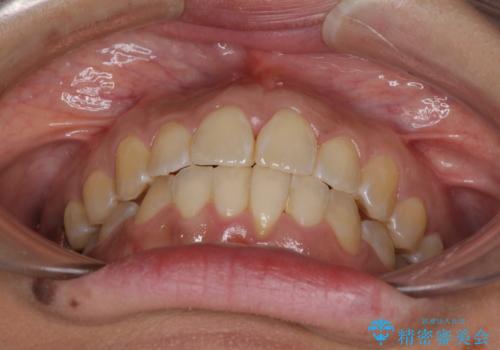

インビザラインによる狭窄歯列の拡大矯正

治療途中で関西に転勤となってしまったため、東京に出張で来るタイミングに合わせて治療を進めることになりました。そのため、治療期間が長くなってしまいましたが、無事に仕上げることができました。